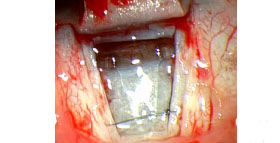

Impianti drenanti